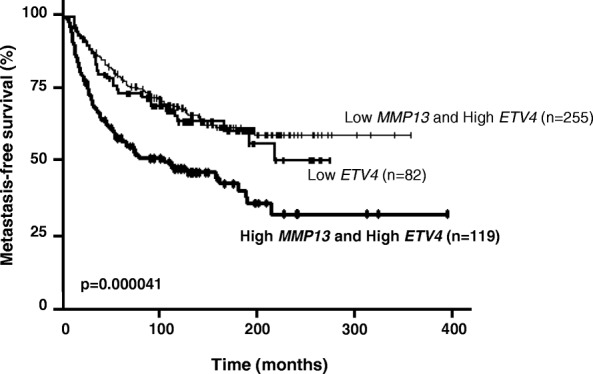

MMP13 and ETV4 expression in breast tumors is associated with a poor prognosis

In order to corroborate the relevance of the phenotypic and mouse in vivo data and to explore the link between ETV4 and MMP13 in human breast cancer, we assessed MMP13 and ETV4 mRNA expression levels in a series of 456 primary unilateral invasive primary breast tumors from patients with known clinical and pathological status and long-term outcome. We used a log-rank test to identify relationships between MFS and MMP13 and/or ETV4 expression. Tumors with the highest levels of MMP13 mRNA (n = 135 [29.6%]) were significantly associated with poor MFS (P = 0.00016), which was not the case for ETV4-expressing tumors (Additional file 9: Figure S7a and b). This result was confirmed in the NKI breast cancer cohort (Additional file 10: Figure S8b and c). Combined analysis (as described in the “Patients and samples for MMP13 and ETV4 expression” subsection of the Methods section above) of MMP13 and ETV4 mRNA expression levels defined three separate prognostic groups of 82 (Low-ETV4), 255 (High-ETV4/Low-MMP13), and 119 (High-ETV4/High-MMP13) patients with significantly different survival (P = 0.000041) (Fig. 7). The patients with the poorest prognosis were observed in the subgroup of 119 of 456 (26.1%) patients characterized by association of high MMP13 and high ETV4 mRNA expression levels. These data were also confirmed in the NKI breast cancer cohort (P = 0.0013) (Additional file 10: Figure S8a). Multivariate analysis using a Cox proportional hazards model was performed to assess the prognostic value for MFS of the parameters found to be significant in univariate analysis (i.e., SBR histological grade, lymph node status, macroscopic tumor size, PR status [Additional file 2: Table S1] and combined MMP13 and ETV4 mRNA levels). The prognostic significance of the lymph node status (P = 0.000016), macroscopic tumor size (P = 0.0028), and combined MMP13 and ETV4 mRNA level was maintained (Additional file 11: Table S2).

Fig. 7.

MMP13 and ETV4 are associated with poor prognosis in breast cancer. Metastasis-free survival (MFS) curves for patients with breast tumors according to Low-ETV4 (n = 82), High-ETV4 and Low-MMP13 (n = 255), or High-ETV4 and High-MMP13 (n = 119) mRNA levels. ****P ≤ 0.0001